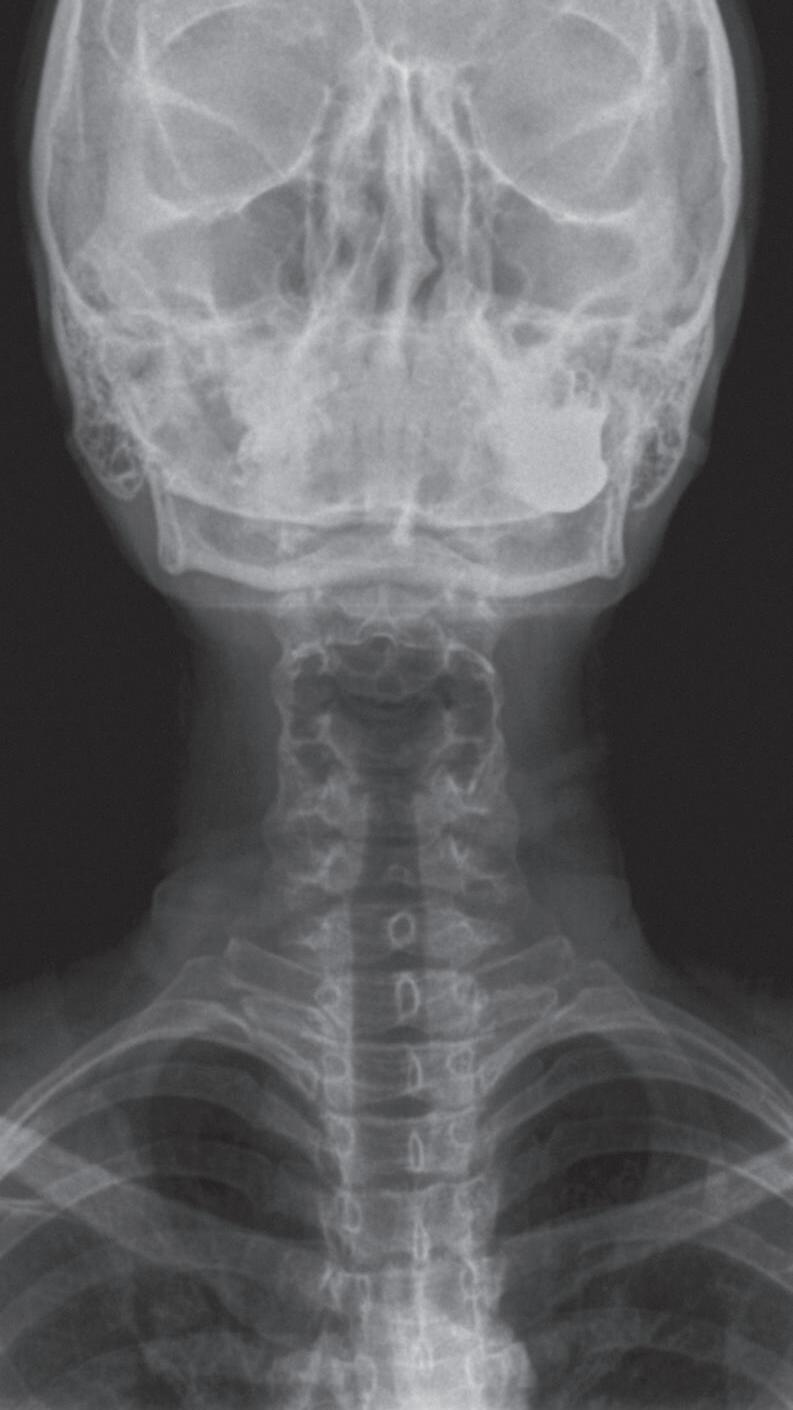

Fig. 1-1. Montagem de duas imagens radiográficas em visão anteroposterior demonstrando o percurso da deglutição desde a cavidade oral até o estômago (a) no adulto e (b) no bebê.

Fig. 1-2. Demonstração das estruturas envolvidas no processo da deglutição nas visões (a) lateral e (b) anteroposterior na imagem radiográfica.